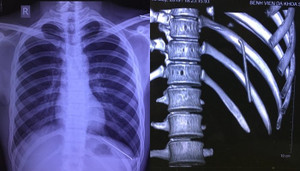

Chiếc đinh tự di chuyển từ vai xuống khoang màng phổi khiến nam thanh niên đau nhiều vùng đáy phổi trái, khó thở, phải nhập viện.